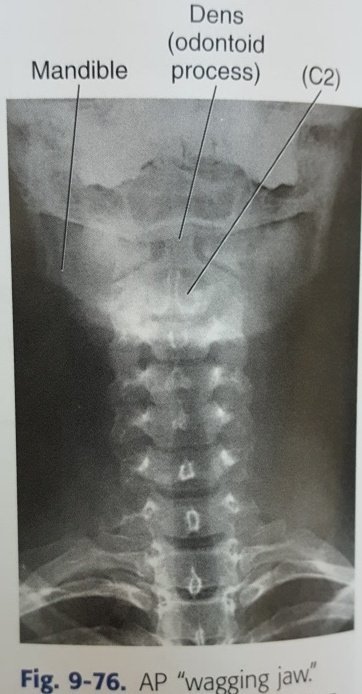

Cervical spine AP open mouth

وهو خاص بإظهار C1 & C2.

الوضع/

•يفتح المريض فمه أقصى مايمكن بتحريك الفك السفلي للأسفل دون تحريك رأسه.

•يبقي اللسان منخفضاً حتى لا يتداخل مع التشريح خلفه.

مركز الشعاع/

في وسط الفم المفتوح عمودياً.

AP axial cervical spine:

•هو الوضع الذي يهمل الكثير منا عمل زاوية فيه فيجعل الشعاع دون زاوية.

•axial

لأن هناك زاوية ١٥°أو٢٠° نحو الرأس بناء على مقدار انحناء الرقبة ووضعية المريض.

(15° supine or less lordotic)

(20° erect or more lordatic)

الهدف هو التغلب على overlapping للفقرات

•نضبط الرأس بحيث لايكون هناك إلتفاف أو ميلان.

•نرفع الذقن حتى يكون الفك السفلي عمودي على الطاولة او موازي لزاوية الشعاع.

C4 =Thyroid cartilage=above sternal notch by 5cm

الزاوية/

كما قلنا سابقاً ١٥-٢٠درجة نحو الرأس بناء على مدى انحناء الرقبة و وضعية المريض

في هذا الوضع الروتيني لن نشاهد الفقرتين C1 and C2

فقط سنشاهد من C3 إلى T2

وذلك بسبب حجب الفك لهما.

ولكن القاعدة الإشعاعية تقول:

(الأشياء المتحركة لاتظهر بوضوح)

لذلك هناك وضع بديل يسمى

AP wagging jaw

أو

Ottonello method

وهو تحريك مستمر للفك أثناء التصوير بشرط عدم تلامس الأسنان